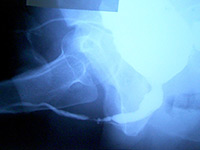

Буккальная 1 этапная уретропластика – Фотогалерея